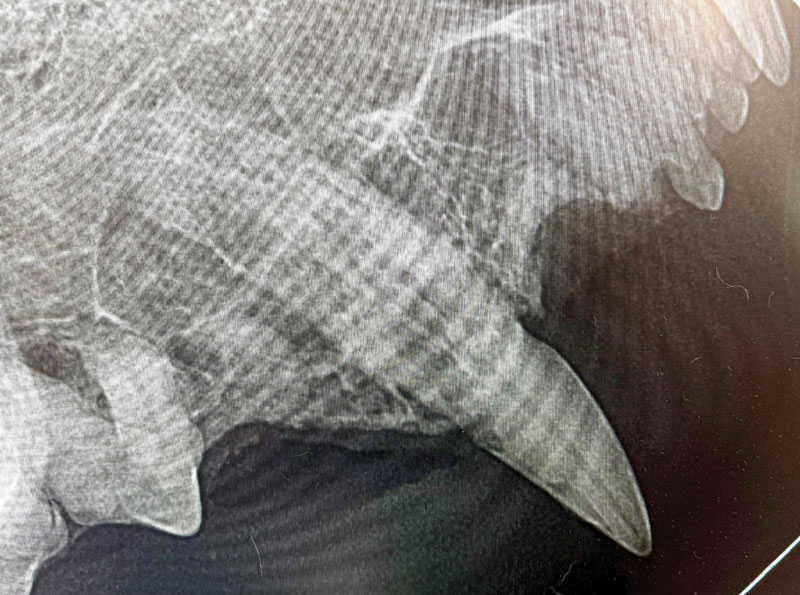

A student named Meredith, who went through the dentistry rotation when I was a professor at Penn, once stated, "It seems gingiva is the 'omentum of the mouth,'" which I felt was a very thoughtful metaphor. Gingiva fills the resorption defect and covers a portion of the cervical crown. Even under anesthesia, lightly running an explorer along the gingival margin may detect an area of resorption, resulting in the tip of the explorer "catching" in the defect and a quiver or chatter of the lower jaw (Figure 1). When tooth resorption reaches the crown and results in exposed dentinal tubules, discomfort occurs when fluids, air, or a dental explorer passes across those exposed dentinal tubules, resulting in the jaw-opening reflex.

Figure 1A. A very subtle area of redness and gingival enlargement at the buccal gingiva margin of tooth 104 in a cat that presented with jaw-opening reflex. Photo courtesy Dr. John R. Lewis

Figure 1B. A dental radiograph shows the full extent of resorption. Photo courtesy Dr. John R. Lewis